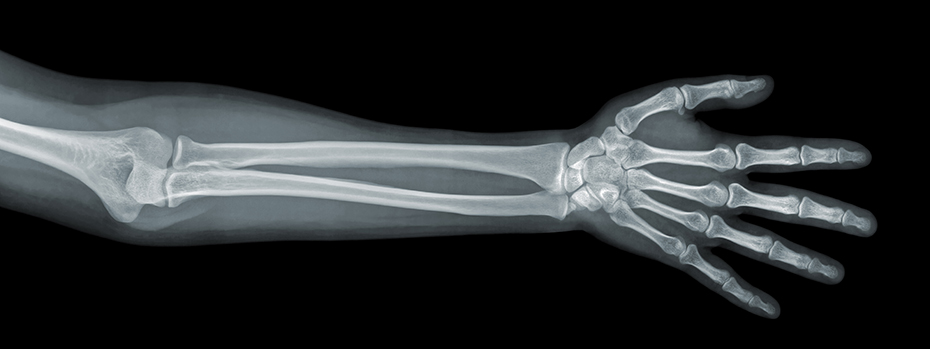

X-ray and Fluoroscopy

X-rays are images of bones and other body parts.

What X-ray is used for

Your doctor may recommend an X-ray to:

- Look at injuries

- Check the size, shape and position of bones or organs

- See how bones or organs are growing